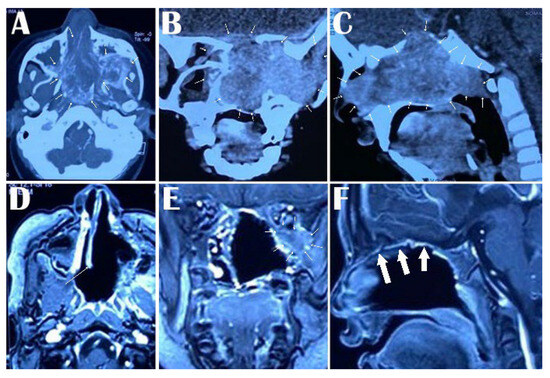

| Case 1 M/17 Y | Stage V | Multilobulated mass occupying the nasopharynx, sphenopalatine fossa, maxillary fossa, right nasal cavity | endoscopic, endonasal, trans maxillary pterygoid approach and middle fossa approach | partial removal | Facial swelling |

| Case 2 M/26 Y | Stage IV | Multilobulated mass occupying the nasopharynx, sphenopalatine fossa, maxillary fossa, right nasal cavity with superior orbital fissure and cavernous sinus | endoscopic, endonasal, trans maxillary pterygoid approach and middle fossa approach | partial removal | Epistaxis |

| Case 3 M/18 Y | Stage V | Multilobulated mass occupying the nasopharynx, sphenopalatine fossa, maxillary fossa, left nasal cavity | endoscopic, endonasal, trans maxillary pterygoid approach and middle fossa approach | partial removal | Epistaxis, facial swelling |

| Case 4 M/16 Y | Stage IV | Multilobulated mass occupying the nasopharynx, sphenopalatine fossa, maxillary fossa, right nasal cavity with superior orbital fissure and cavernous sinus | endoscopic, endonasal, trans maxillary pterygoid approach and middle fossa approach | total removal | Epistaxis, nasal deformity |

| Case 5 M/17 Y | Stage V | Multilobulated mass occupying the nasopharynx, sphenopalatine fossa, maxillary fossa, right nasal cavity with superior orbital fissure and cavernous sinus | endoscopic, endonasal, trans maxillary pterygoid approach and middle fossa approach | partial removal | No complication |

| Case 6 M/17 Y | Stage III | Multilobulated mass occupying the nasopharynx, sphenopalatine fossa, maxillary fossa, left nasal cavity | endoscopic, endonasal, trans maxillary pterygoid approach | partial removal | No complication |

| Case 7 M/17 Y | Stage V | Multilobulated mass occupying the nasopharynx, sphenopalatine fossa, maxillary fossa, right nasal cavity with superior orbital fissure and cavernous sinus | endoscopic, endonasal, trans maxillary pterygoid approach and middle fossa approach | total removal | Epistaxis, nasal deformity |

| Case 8 M/24 Y | Stage IV | Multilobulated mass occupying the nasopharynx, sphenopalatine fossa, maxillary fossa, right nasal cavity | endoscopic, endonasal, trans maxillary pterygoid approach and middle fossa approach | total removal | Epistaxis |

| Case 9 M/17 Y | Stage III | Multilobulated mass occupying the nasopharynx, sphenopalatine fossa, maxillary fossa, left nasal cavity | endoscopic, endonasal, trans maxillary pterygoid approach | total removal | Epistaxis, facial swelling |

| Case 10 M/16 Y | Stage IV | Multilobulated mass occupying the nasopharynx, sphenopalatine fossa, maxillary fossa, right nasal cavity with superior orbital fissure and cavernous sinus | endoscopic, endonasal, trans maxillary pterygoid approach and middle fossa approach | partial removal | No complication |

| Case 11 M/21 Y | Stage V | Multilobulated mass occupying the nasopharynx, sphenopalatine fossa, maxillary fossa, right nasal cavity | endoscopic, endonasal, trans maxillary pterygoid approach and middle fossa approach | total removal | No complication |

| Case 12 M/18 Y | Stage IV | Multilobulated mass occupying the nasopharynx, sphenopalatine fossa, maxillary fossa, left nasal cavity | endoscopic, endonasal, trans maxillary pterygoid approach and middle fossa approach | partial removal | Facial swelling |

| Case 13 M/18 Y | Stage III | Multilobulated mass occupying the nasopharynx, sphenopalatine fossa, maxillary fossa, right nasal cavity with superior orbital fissure and cavernous sinus | endoscopic, endonasal, trans maxillary pterygoid approach | total removal | No complication |

| Case 14 M/16 Y | Stage IV | Multilobulated mass occupying the nasopharynx, sphenopalatine fossa, maxillary fossa, right nasal cavity | endoscopic, endonasal, trans maxillary pterygoid approach and middle fossa approach | total removal | No complication |

| Case 15 M/17 Y | Stage V | Multilobulated mass occupying the nasopharynx, sphenopalatine fossa, maxillary fossa, right nasal cavity with superior orbital fissure and cavernous sinus | endoscopic, endonasal, trans maxillary pterygoid approach and middle fossa approach | total removal | No complication |